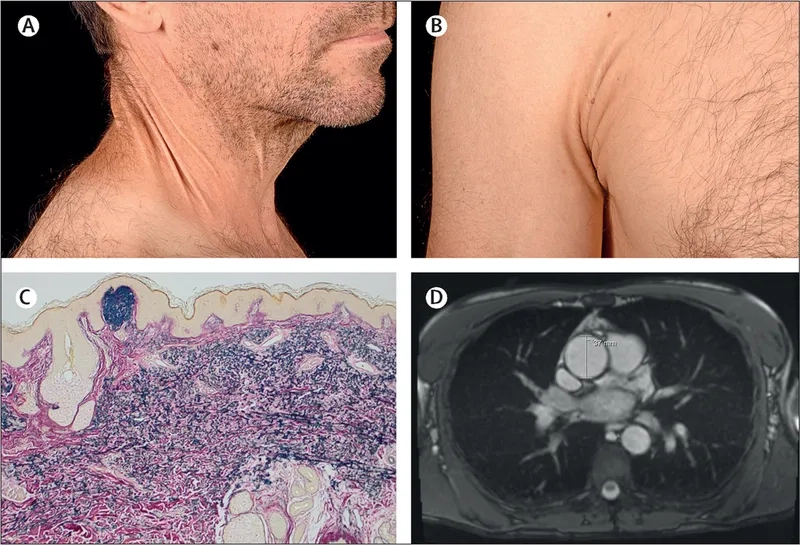

• A highly specific sign is the presence of Kayser-Fleischer rings, which are brownish-gold rings that appear around the edge of the cornea in the eyes.

Kayser-Fleischer rings in Wilson's disease eyes

Eye exam showing Kayser Fleischer rings